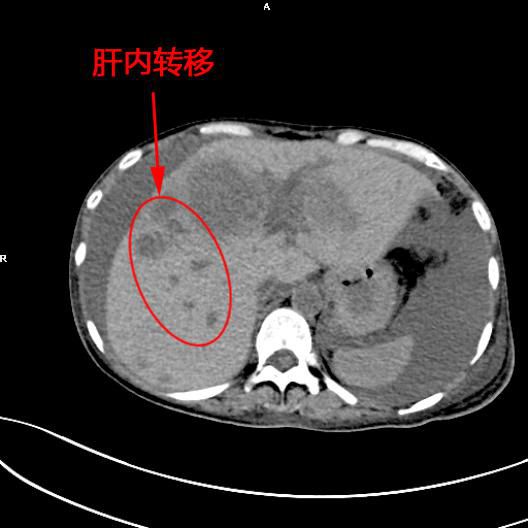

患者陳女士,57歲,汕頭潮南人,2個月前出現右上腹痛,在汕頭大型三甲醫院确診爲膽囊癌,因腫瘤爲晚期,已擴散至肝髒、十二指腸,患者放棄在汕頭治療,回家後自行采用中藥治療。近期右上腹痛加重,反複排黑便,遂來我院住院,診斷爲膽囊癌伴活動性出血。

5月11日下午,内三科主任李旭丹、影像科副主任胡志華上台施術。通過粵東領先的飛利浦DSA造影顯示,患者腫瘤供血血管豐富,膽囊動脈造影可見腫瘤染色明顯,有造影劑外溢,提示部分血管末梢有破裂出血現象,探查胃十二指腸動脈及腸系膜上動脈未見出血征像,豐富的血供使腫瘤能獲取大量的營養快速生長,血管末梢的破裂出血導緻患者反複黑便。

李旭丹主任在DSA引導下找到腫瘤的供血動脈——膽囊動脈,通過股動脈穿刺置入微導管将栓塞材料送達并釋放于腫瘤供血動脈,成功将動脈堵住,掐斷了腫瘤的供血。手術達到了預期目的,不但膽囊出血得到根除,也阻斷了腫瘤的營養供應,達到“餓”死腫瘤的目的,同時在腹腔幹灌注化療藥治療轉移病竈。